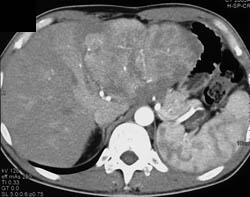

Hepatoma